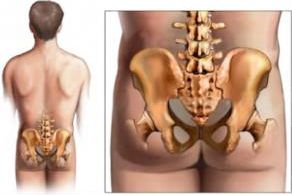

Poprzez wiele czynników np. wagę, predyspozycje dziedziczne, ukształtowanie anatomiczne – miednica może występować w kilku pozycjach.

Mówiąc o pozycjach – wyróżniamy trzy konkretne, w których porównuje się miednicę do wiadra... Zobaczcie:

Analizując kolejno:

1. Przodopochylenie miednicy – Miednica przechyla się do przodu.

Odstający brzuch, bardzo duża lordoza w odcinku lędźwiowym kręgosłupa (wgięcie do środka), wypinanie pośladków, pochylenie ciała do przodu. Daje to: bóle pleców w lędźwiach, problemy układu wydalniczego, często mrowienia i drętwienia nóg.

2. Pozycja neutralna miednicy jest wtedy, kiedy całe nasze ciało jest swobodne. Żadne mięśnie nie są przykurczone, a żadne też nadmiernie rozciągnięte. Proces funkcjonowania układu krwionośnego jest stabilny.

3. Tyłopochylenie miednicy – proces odwrotny do przodopochylenia. Tu miednica jest skierowana ku tyłowi. Tu występuje ogromna kifoza odcinka piersiowego kręgosłupa (co widac na obrazku ponizej postać 1 ), pośladki zanikają, lędźwie są spłaszczone.

Obrazek powyżej naocznie pokazuje wam pozycje ustawienia miednicy i ich wpływ na całokształt naszego ciała.

W tym przypadku pozycja prawidłowa to postać 3 na rycinie.

Postać 1 to TYŁOPOCHYLENIE, a postać 2 to PRZODOPOCHYLENIE.

Co to daje? ZNACZNIE większy procent ludzi ma ukształtowanie miednicy dalekie od ideału. Często cegiełkę do nieprawidłowego ułożenia dodaje pozycja siedzenia np. W pracy (siedzenie powyżej 5 godzin).